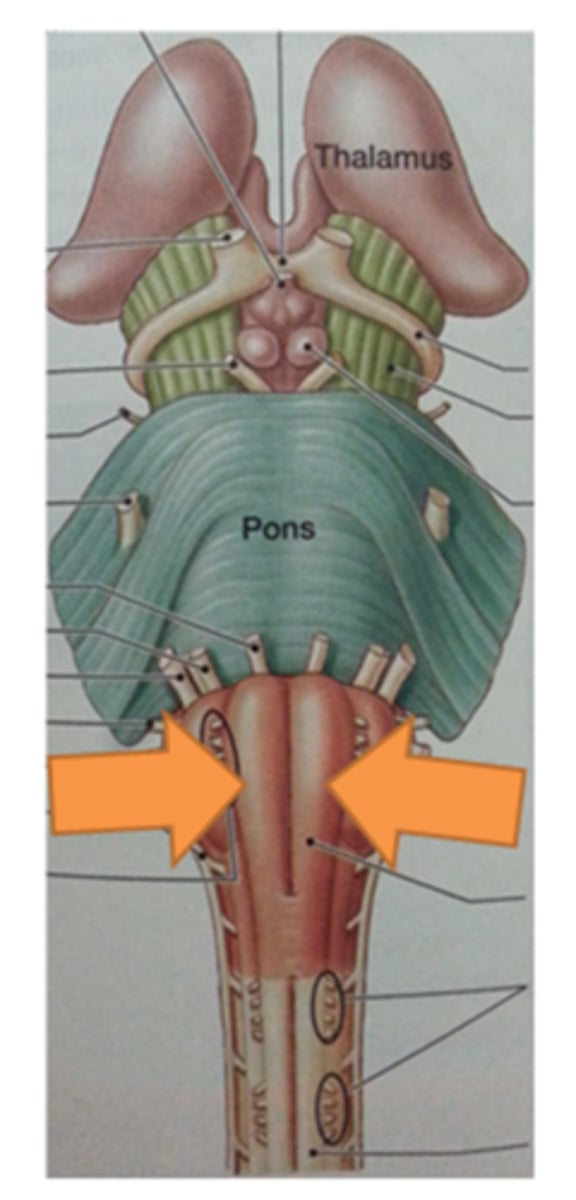

two ridges of tissue on the ventral aspect of the medulla, separated from each other by the ventral median fissure

pyramids

area where most corticospinal fibers decussate over the lower medulla, therefore obscuring the ventral median fissure

pyramidal decussation

elongated mounds of tissue lateral to the medullary pyramids

olives

vertical groove dorsolateral to the inferior olive on each side that gives rise to CN IX and X

postolivary sulcus

white matter stalks that connect the medulla to the cerebellum

**these help to form the lateral walls of the caudal portion of the 4th ventricle

inferior cerebellar peduncles

What is the superior boundary of the pons?

isthmus of the brain stem (between pons and cerebral peduncles)

What is the inferior boundary of the pons?

pontomedullary junction

refers to the large round protuberance on the ventral pons that represents a "bridge" of horizontally oriented fibers connecting the right and left sides

basilar portion

longitudinal midline groove of the pons that is the superior continuation of the ventral median sulcus/fissure, containing a namesake artery

basilar sulcus

white matter stalks that connect the pons to the cerebellum

middle cerebellar peduncles

What is the only cranial nerve that attaches to the pons?